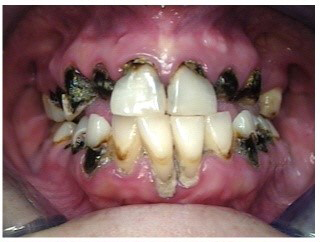

Often, the most visually striking manifestation of long-term meth use—known as “meth mouth”—is caused by the lack of saliva combined with an increase in soda drinking and extremely poor oral hygiene. This typically leads to meth abusers experiencing a large amount of caries. Decay begins with occlusal and facial caries and progresses rapidly, decaying to the bone level and often leaving only roots (Figure 1 through Figure 3).16

Fig 2. Gross oral destruction was the result of more than 20 years of meth use in this 41-year-old woman.

Figure 2

Fig 4 through Fig 6. Patient’s oral condition after 6 years of meth use.